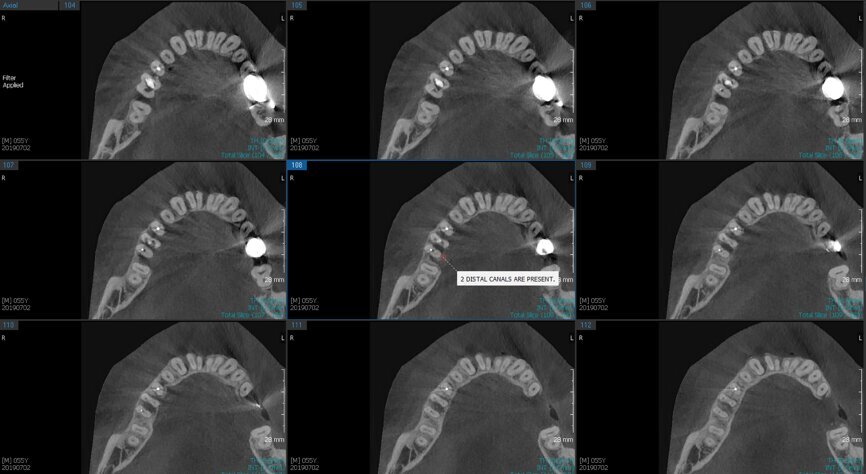

Fig.2a: Pre-op CBCT images of tooth #46: No obturation material in the distal and mesiobuccal canal (a); scanty obturation of the canals and breach of the floor of the pulp chamber, no obturation beyond a few millimetres down the orifice (b & c); radiolucency in the furcation area and periapical region of both roots (d -g).

Fig.2b: Pre-op CBCT images of tooth #46: No obturation material in the distal and mesiobuccal canal (a); scanty obturation of the canals and breach of the floor of the pulp chamber, no obturation beyond a few millimetres down the orifice (b & c); radiolucency in the furcation area and periapical region of both roots (d -g).

Fig.2c: Pre-op CBCT images of tooth #46: No obturation material in the distal and mesiobuccal canal (a); scanty obturation of the canals and breach of the floor of the pulp chamber, no obturation beyond a few millimetres down the orifice (b & c); radiolucency in the furcation area and periapical region of both roots (d -g).

Fig.2d: Pre-op CBCT images of tooth #46: No obturation material in the distal and mesiobuccal canal (a); scanty obturation of the canals and breach of the floor of the pulp chamber, no obturation beyond a few millimetres down the orifice (b & c); radiolucency in the furcation area and periapical region of both roots (d -g).

Fig.2e: Pre-op CBCT images of tooth #46: No obturation material in the distal and mesiobuccal canal (a); scanty obturation of the canals and breach of the floor of the pulp chamber, no obturation beyond a few millimetres down the orifice (b & c); radiolucency in the furcation area and periapical region of both roots (d -g).

Fig.2f: Pre-op CBCT images of tooth #46: No obturation material in the distal and mesiobuccal canal (a); scanty obturation of the canals and breach of the floor of the pulp chamber, no obturation beyond a few millimetres down the orifice (b & c); radiolucency in the furcation area and periapical region of both roots (d -g).

Fig.2g: Pre-op CBCT images of tooth #46: No obturation material in the distal and mesiobuccal canal (a); scanty obturation of the canals and breach of the floor of the pulp chamber, no obturation beyond a few millimetres down the orifice (b & c); radiolucency in the furcation area and periapical region of both roots (d -g).

When I had a close look at the preoperative radiograph from the referring dentist (Fig. 1a), I observed that there was insufficient obturation of the mesial canals and almost no obturation of the distal canal. Both roots displayed periapical radiolucency. The clinical examination revealed a Grade I mobility, and the tooth was tender to percussion. The periodontal examination ruled out any pockets and loss of attachment. We took an intra-oral periapical radiograph (Fig. 1b), from which we observed the loss of coronal structure and a large radiolucent area over the furcation area and the periapical area of both the mesial and the distal roots. A CBCT scan of tooth #46 was advised to check for any details that may have been missed in the intra-oral periapical radiograph (Figs. 2a–g). From the CBCT scan, it could be observed that there was inadequate obturation of the distal canal on the horizontal plane, no obturation beyond the middle third in the mesial canals and a breach of the floor of the pulp chamber. The questionable prognosis was explainedto the patient, and written consent was obtained.